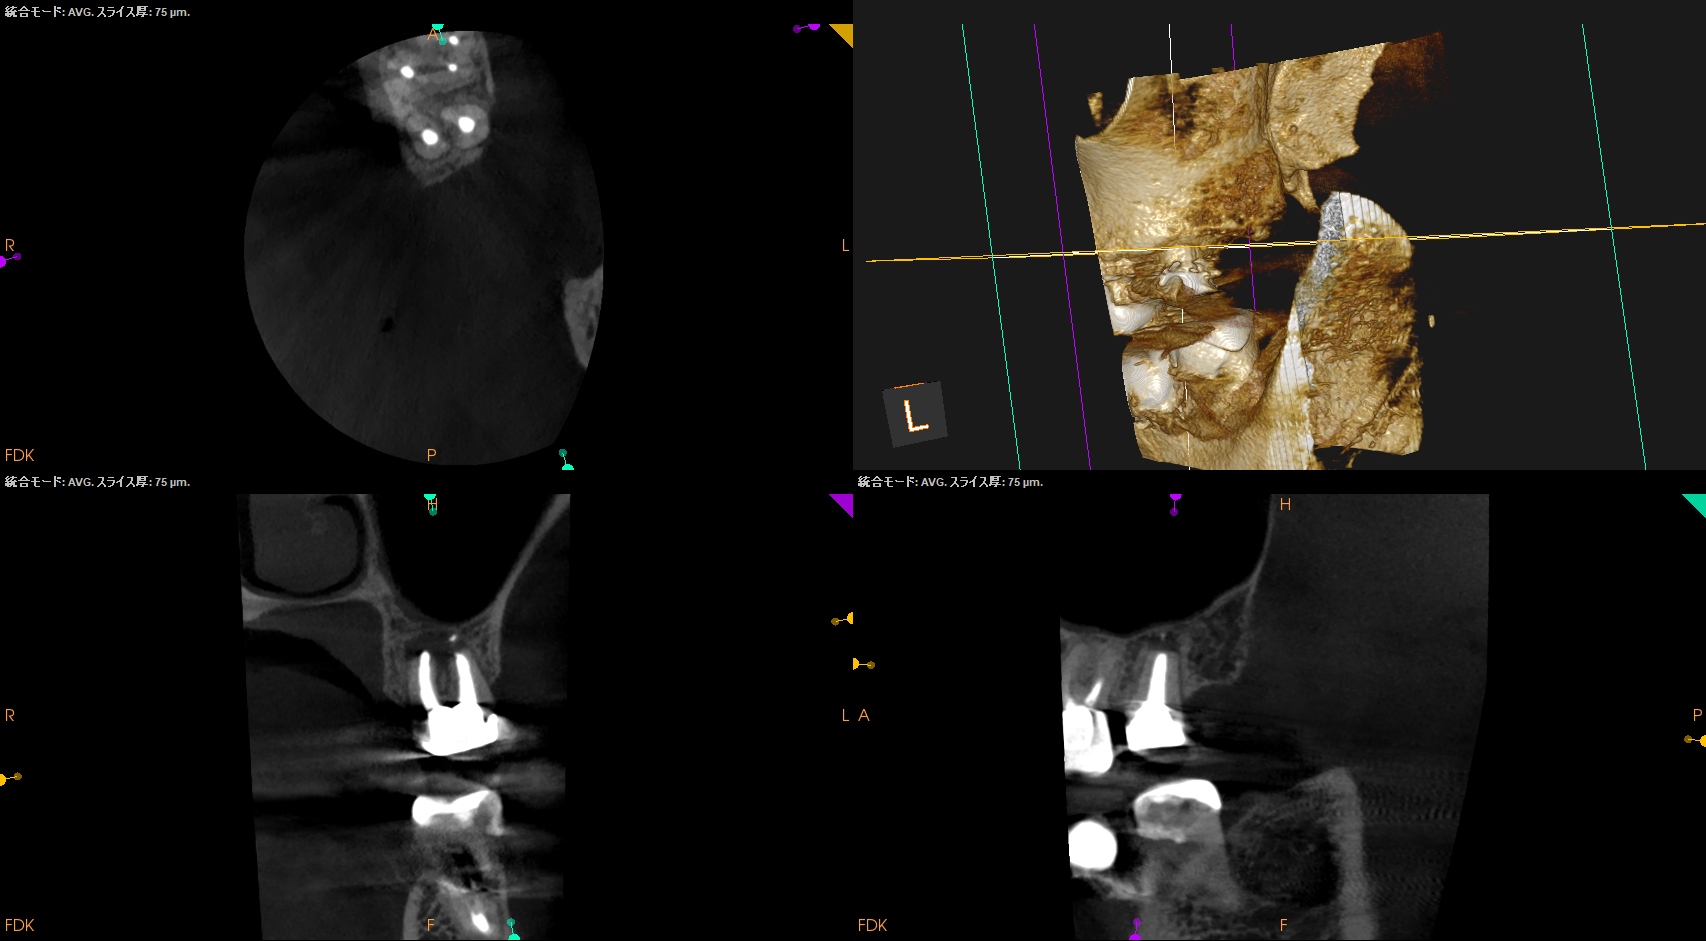

術後にPA, CBCTを撮影した。

この1ヶ月後に再診があり、歯牙をチェックした。

#15 Intentional Replantation 1M recall(2026.1.21)

動揺も生理的な範囲内だ。

ということで、プロビジョナルレストレーションの装着を依頼した。